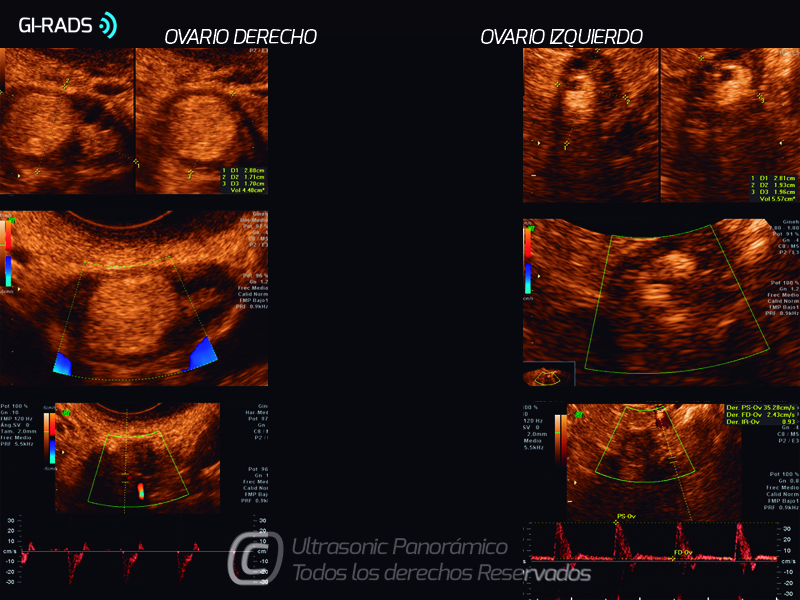

Patologías Benignas – Teratoma Maduro

• Patologías Benignas – Teratoma Maduro